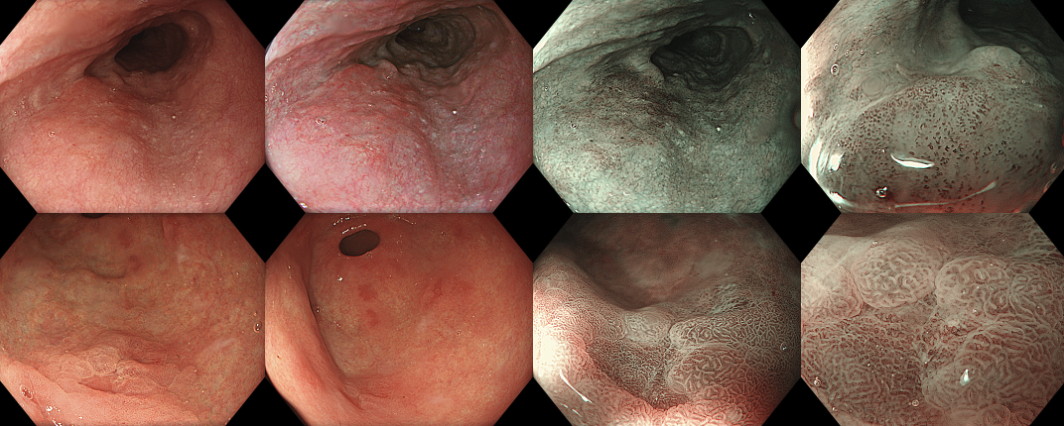

Advanced endoscopic techniques such as chromoendoscopy and magnifying NBI play a key role in identifying and evaluating lesions, thereby informing an appropriate resection strategy.